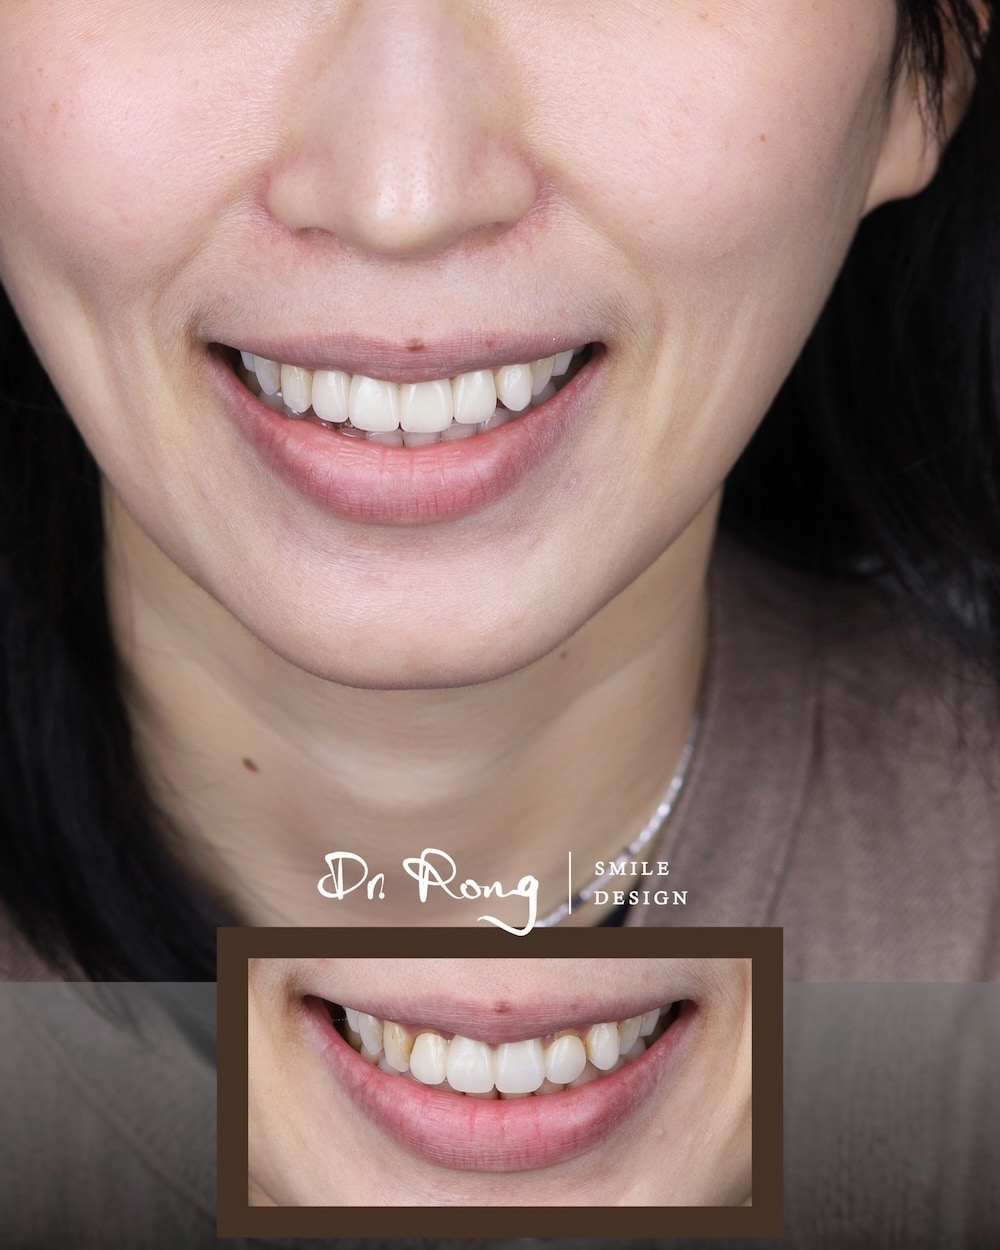

許多患者來到診間,並非因為「牙齒不夠白」,而是因為舊假牙「太像假的」。門牙假牙顏色不自然、偏白甚至呈現死白,或是假牙邊緣不密合、出現黑邊,都會讓笑容看起來不協調。

真正的數位美學設計,在門牙假牙重做過程中,不只是更換材料,而是透過精準的軸向校正與牙齦健康管理,讓門牙重新融入面部比例,達成局部換新卻完全不突兀的自然感。

在這個案例中,患者帶著對舊假牙的不滿意來到悅庭找我。透過數位口腔掃描與臨床觀察,我們發現過往治療留下了三個美觀與健康上的遺憾:

- 假牙顏色不自然、偏灰:傳統材質缺乏真牙的透光感,在自然光下容易顯得生硬突兀。

- 牙齦發炎與邊緣發黑:舊假牙邊緣不密合,長期刺激導致牙齦紅腫發炎,甚至出現萎縮與邊緣黑影。

- 門牙角度與弧度不理想:假牙軸向過度外翻,且整體弧度偏斜,讓笑容失去了該有的溫潤感。

在門牙全瓷冠重建過程中,我們微調了每一顆牙齒的生長角度。將原本過度外傾的門牙向內收斂,並校正傾斜的齒緣弧度。這僅僅 4 顆牙齒的改變,就讓患者整體的氣質從「生硬」變得「柔和」。

我們選用能遮住內層齒色卻也足夠透光的陶瓷材質,模擬自然齒質的漸層色澤。透過精密的色彩校正,確保這 4 顆新成員能完美隱身在其他天然牙齒中,達成真正「融入式」的美感。

看著患者在鏡子前露出不再遮掩的燦爛笑容,這就是美學牙醫最有成就感的時刻。這不只是 4 顆門牙的更新,更是一次自信心的重塑。